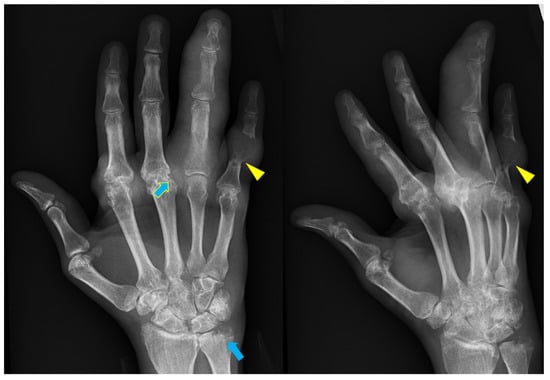

5. Psoriatic Arthritis (PsA)